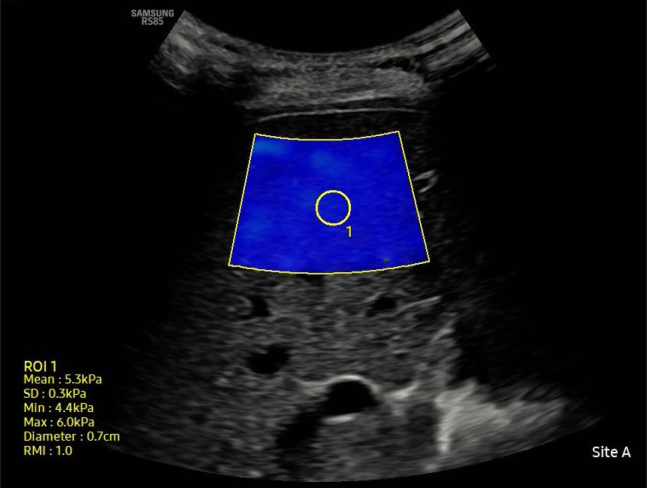

Methods: A total of 76 obese children and adolescents aged 6-18 years, with body mass index percentiles >95th, were included in the study. Patients with metabolic syndrome, diabetes mellitus, and chronic liver disease were excluded. A control group of 44 patients of healthy and normal-weight children was included. Laboratory values from the past month were analyzed using patient records. Shear wave elastography and ultrasound examinations were performed on a single device by the same experienced radiologist.

Results: The systemic immune-inflammation index and pan-immune inflammation values were significantly higher in obese patients with hepatic steatosis compared to obese patients without hepatic steatosis (p <0.001). Liver stiffness values were significantly higher in steatotic patients compared to nonsteatotic patients (p <0.001). A significant difference was observed between hepatic steatosis grades in terms of immune-inflammation index and pan-immune inflammation value values (p <0.001). There was a strong, positive, statistically significant correlation between liver stiffness and immune-inflammation index and pan-immune inflammation value (p <0.05).

Conclusions: Immune-inflammatory biomarkers and shear wave elastography may provide valuable insights into the diagnosis and follow-up of inflammation and fibrosis in the evaluation of hepatic steatosis in obese children and adolescents.